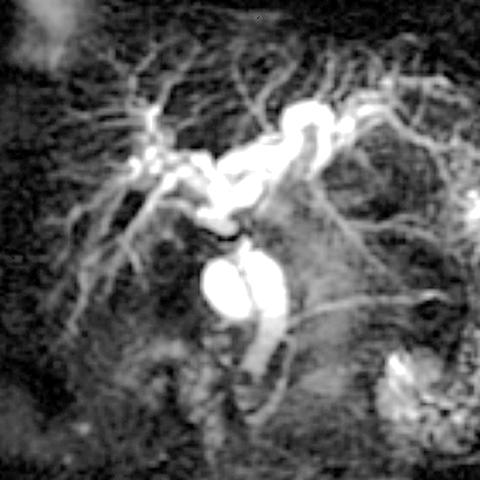

Ductal Calculus [2 of 2]